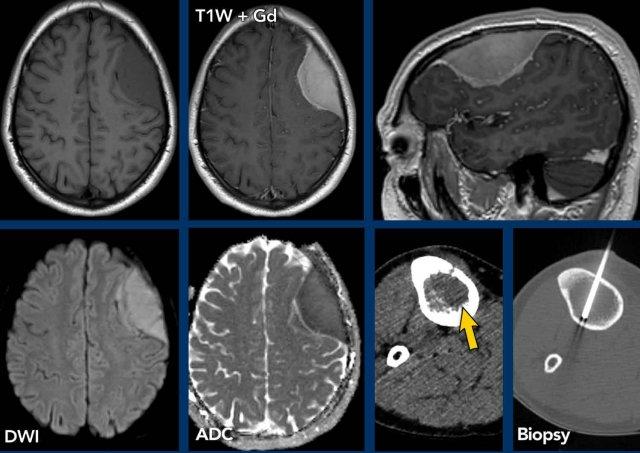

Các hình ảnh này của bệnh nhân có áp xe vùng đỉnh.

Hình ảnh

Áp xe biểu hiện hạn chế khuếch tán trung tâm với thành ngấm thuốc tương đối dày.

Đầu mũi tên màu vàng chỉ vào lớp ngấm thuốc mỏng của thành não thất.

Kết luận

Áp xe lan vào trong não thất, dẫn đến viêm não thất.

Các hình ảnh này của bệnh nhân nam 63 tuổi, có áp xe não nhỏ (mũi tên vàng) tại trung tâm bán bầu dục bên phải.

Lưu ý có sự xâm lấn não thất đáng kể.

Bên cạnh ngấm thuốc thành não thất, còn ghi nhận hạn chế khuếch tán trong áp xe và trong lòng não thất (đầu mũi tên).